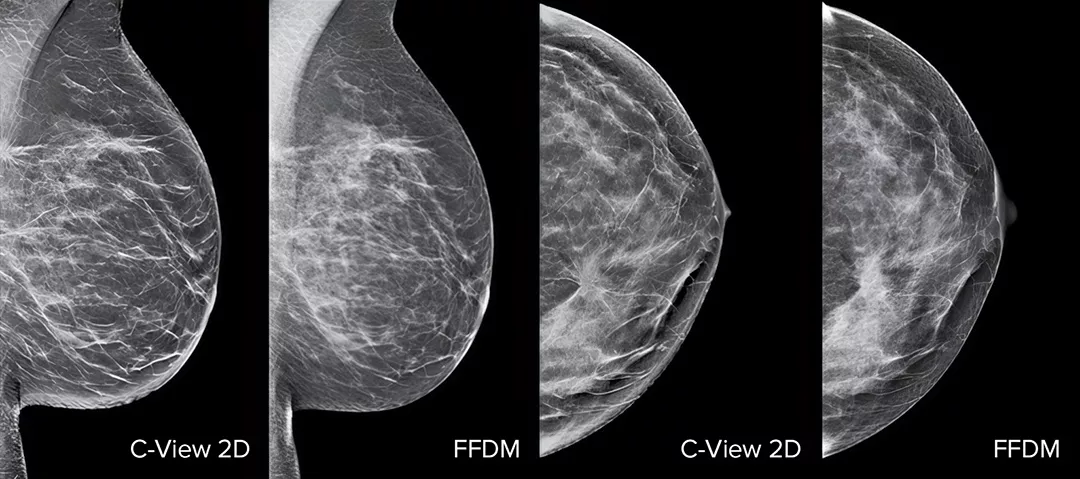

Architectural distortions, mass lesions, and bright spots commonly found in microcalcifications are more visible in the C-View 2D image than on the traditional FFDM 2D images or tomo slices.4,6-9

The Proof is in the Details

C-View 2D images are clinically proven3,5 and can potentially replace the FFDM images within a tomosynthesis screening exam. The images are also a navigational aid to the tomosynthesis slice review. Published studies show that the low dose 3D Mammography exam finds invasive cancer earlier, while also reducing false positive recall rates compared to 2D alone.4,5,7

Architectural distortions, mass lesions, and bright spots commonly found in microcalcifications, are more visible in the C-View 2D image than on the traditional FFDM 2D image or tomo slice.4,6-9

Images of breast x-ray